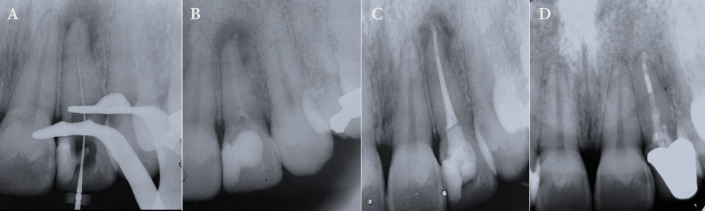

Endodontic management of teeth afflicted with pulp canal obliteration faces a challenge due to the heightened risk of complications including excessive wear, perforation, and suboptimal chemomechanical preparation. This report aims to elucidate the clinical endodontic strategy employed in addressing pulp canal obliteration after a history of dental trauma and an associated periradicular lesion in an upper lateral incisor. A patient visited the dental emergency department with symptoms of apical swelling, acute persistent pain, and discoloration of tooth 22. Following comprehensive clinical evaluation and cone-beam computed tomography, the diagnosis of pulp canal obliteration involving the cervical and middle thirds of the tooth, alongside an acute periradicular abscess was established. Root canal was accessed using tomographic image planning, augmented by loupe magnification and ultrasonic instrumentation. Precise identification of the access cavity was radiographically confirmed, preceded by thorough irrigation with 2.5% sodium hypochlorite and subsequent cervical and middle third preparation. Verification of the working length by an electronic apex locator ensured precise apical preparation, followed by passive ultrasonic irrigation to optimize disinfection and to enhance penetrability of intracanal calcium hydroxide medication, administered for 15 days to eliminate microbial invasion. Upon resolution of symptoms, root canal obturation employing thermo-mechanical compaction and coronal sealing with composite resin was accomplished. Radiographic assessment after a one-year interval presented evidence of lesion regression and bone repair. Subsequent cone-beam computed tomography imaging at the three-year follow-up confirmed complete healing of the periradicular tissues, attesting to the efficacy of the endodontic intervention.